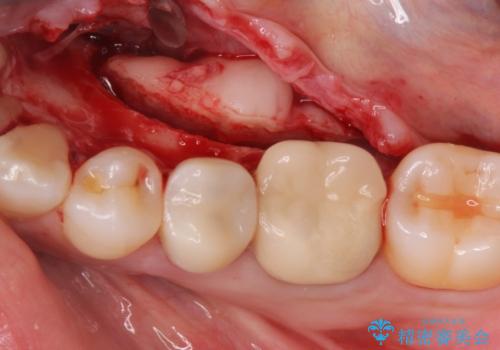

骨隆起除去

- 骨隆起が舌にあたり不快感があるので骨隆起をとりたくて来院。

静脈内鎮静麻酔下で骨隆起を除去を行いました。